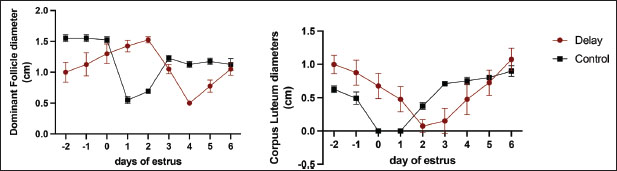

FDD and CL measurements

In contrast, the CL sizes of DO cows were higher than those of NO cows, particularly in the pre-estrus. Table 2 shows no significant differences in follicle size or CL at post-onset estrus. Interestingly, DO cows maintained a follicular development pattern until days 3–4 after onset-estrous onset (Figs. 1 and 2), whereas the follicle size of NO cows shrank and even disappeared near estrous onset (day 0). Moreover, in DO cows, the CL did not directly undergo luteolysis at the onset of estrus and remained for several days, in contrast to NO cows, where the CL had been lysed a while before the onset of estrus. Furthermore, a few days from d-5 to d-6 after ovulation, both DO and NO cows had similar CL sizes (Table 2 and Fig. 2).

Fig. 2. Comparative analysis of ovarian size, focusing on the dimensions of follicles and the corpus luteum, in cows exhibiting ovulation delay versus normal cows. Measurements were taken at multiple reproductive stages: before estrus, at the onset of estrus, and throughout the luteal phase. This figure illustrates the differences in ovarian morphology associated with ovulation timing, highlighting potential physiological variations between the two groups across the estrous cycle phases.